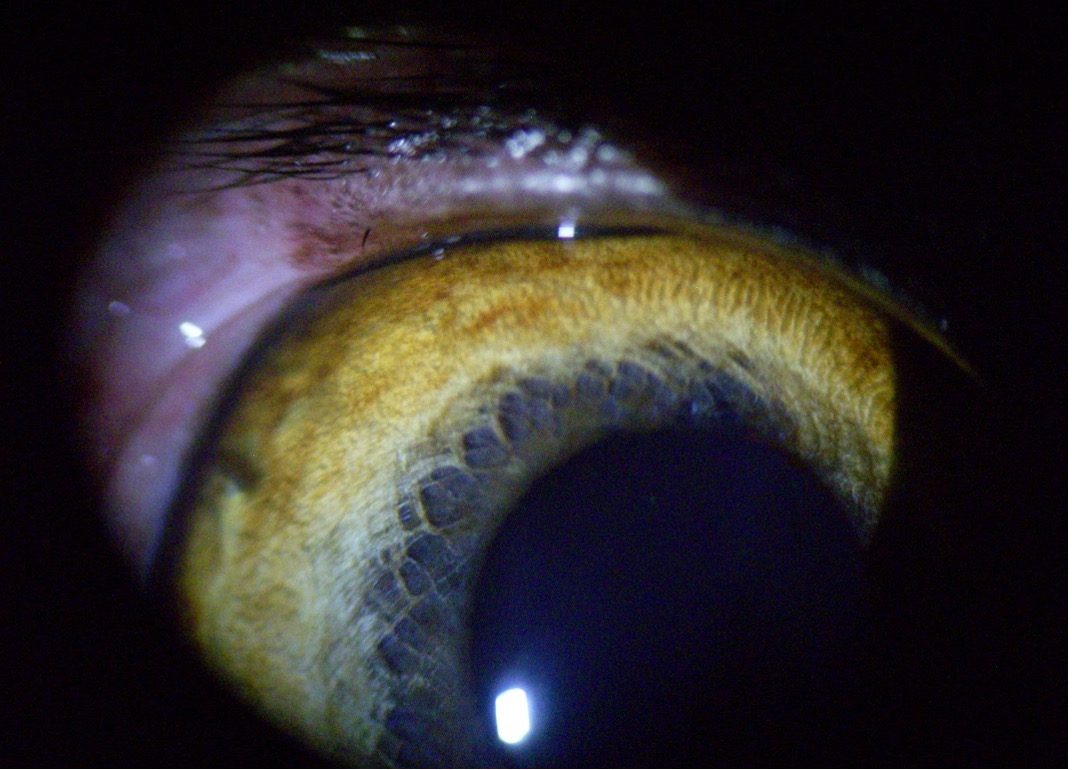

- Distichiasis – Ebben az esetben a kutya normálisan elhelyezkedő szemhéjszélén (általában az alsó vagy felső szemhéjon) plusz szempillák nőnek, mégpedig a Meibom-mirigyek nyílásaiból. Ezek a pillák gyakran rossz irányba, a szaruhártya felé nőnek és dörzsölik a szemfelszínt.

- Ectopiás cilia – Ez egy súlyosabb forma, amikor egy vagy több szempilla a szemhéj belső oldalán, a kötőhártya felől nő, közvetlenül a szaruhártyához érve. Ezek a szőrszálak állandó irritációt okoznak, és gyakran fekély kialakulásához vezetnek.

A distichiasis és az ectopiás cilia szemészeti vizsgálattal ismerhető fel. Ehhez gyakran réslámpát vagy nagyítót, valamint fluoreszcein-es festést alkalmaznak a szaruhártya elváltozásainak vizsgálatához.

Egyes szempillák nagyon finomak és alig láthatók, ezért a tapasztalt szemész állatorvos szerepe kiemelten fontos a diagnózisban.